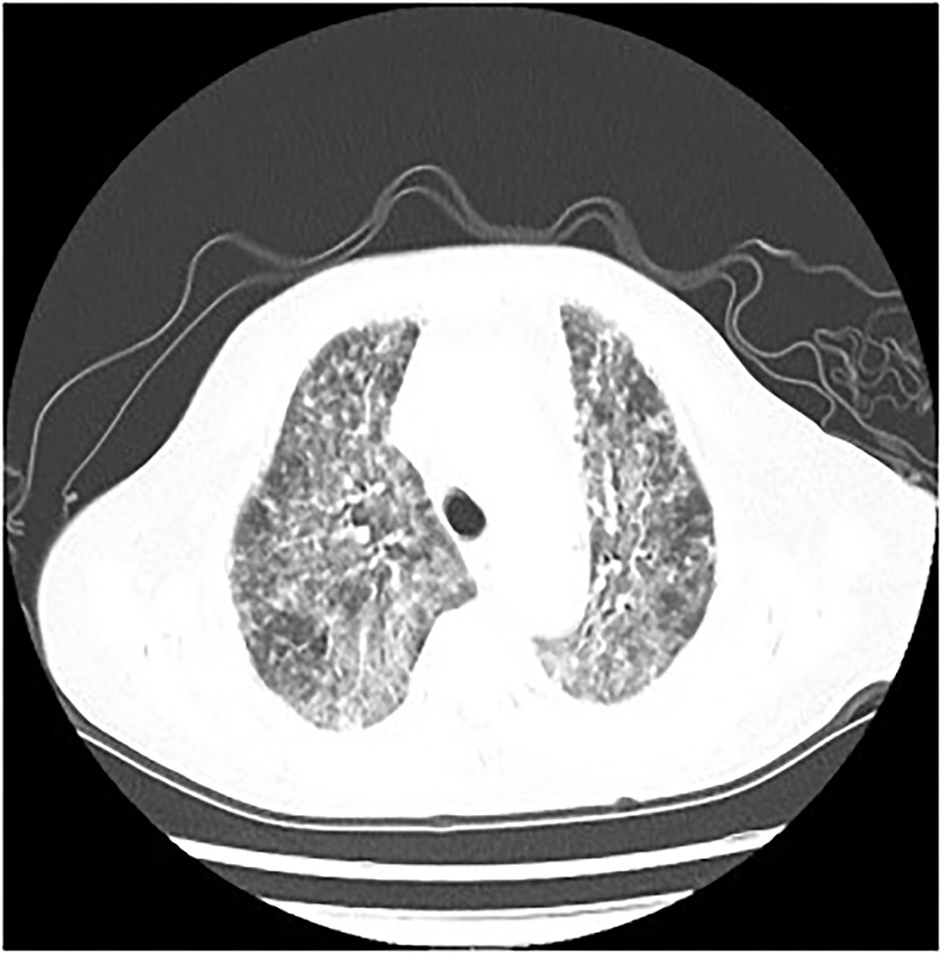

Figure 3

P. jirovecii appearances on Chest CT scan in patient 2 as multiple patchy and flocculent high-density shadows in both lungs.

Patients with HIV who are also infected with P. jirovecii usually present with fever, dry cough, dyspnea, and ground-glass opacity (GGO) imaging on chest CT. According to our observations, the main manifestations of the patients were fever, chest tightness, and dyspnea. In addition, chest CT showed multiple patchy, flocculent, and grid-like high-density shadows. Due to its atypical early symptoms and radiographic findings, it is easy for it to be clinically ignored, which eventually leads to delayed disease recognition and treatment. Although our clinicians did empirically administer antifungals, the outcome of patients was not satisfactory. All four of the patients in this study rapidly deteriorated and were transferred to the ICU for severe respiratory failure, pulmonary infection, and mechanical ventilation. Therefore, we need to identify the etiology as soon as possible so as to make an early diagnosis and begin early treatment.